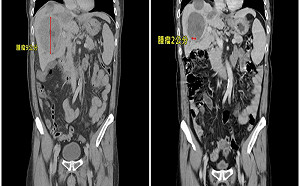

男患肝癌轉移「肺部佈滿數十顆腫瘤」 用對療法僅剩兩顆